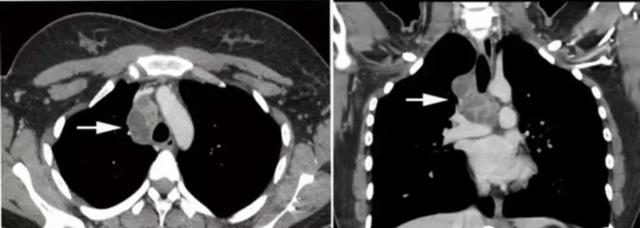

肺结核的分型诊断标准,肺结核的分型及影像学表现

胸内淋巴结结核 胸部正位片,右上纵隔旁可见软组织影突向肺野,边界清晰